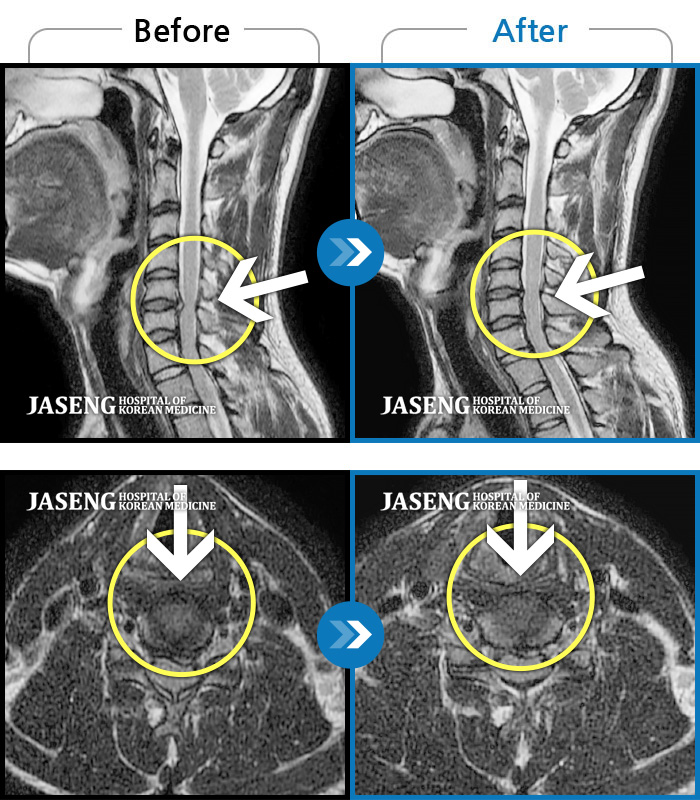

목디스크

도움받은 사례

인천 · 강아현 원장

처음 내원시 목에서 등으로 이어지는 통증 및 우측 팔 저림 증상이 심했고, 약간의 근력저하도 동반되어 일상생활이 어려운 상태였습니다.

촬영시기

2024.04.06 ~ 2024.11.16

2024.11.22